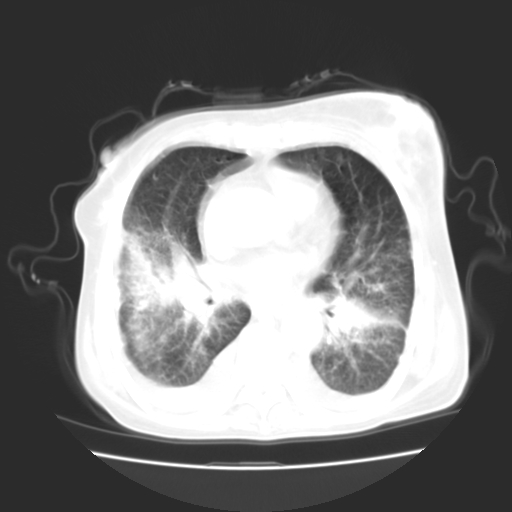

女70y乳腺ca(针吸活检)

癌性淋巴管炎,肝脏转移,瓷胆囊

1)左侧乳腺癌并左侧腋窝及纵隔淋巴结转移,两肺淋巴道转移(癌性淋巴管炎),肝脏多发性转移。2)双侧胸腔积液。3)慢性胆囊炎。

5、肝转移瘤;

6、瓷胆囊。

1)左侧乳腺癌并左侧腋窝及纵隔淋巴结转移,肝脏多发性转移。2)双侧胸腔积液伴双肺蝶翼样磨玻璃高密度影,双侧肺门血管影增粗(图像不全,肺门层面没纵隔窗),考虑心功能不全所致。3)慢性胆囊炎伴壁钙化。